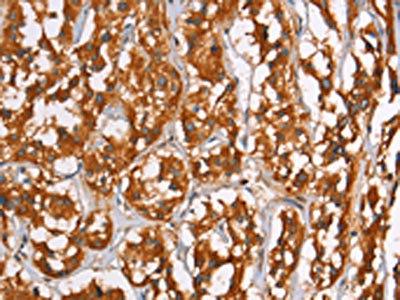

The image on the left is immunohistochemistry of paraffin-embedded Human thyroid cancer tissue using CSB-PA920084(PLIN2 Antibody) at dilution 1/40, on the right is treated with synthetic peptide. (Original magnification: ×200)